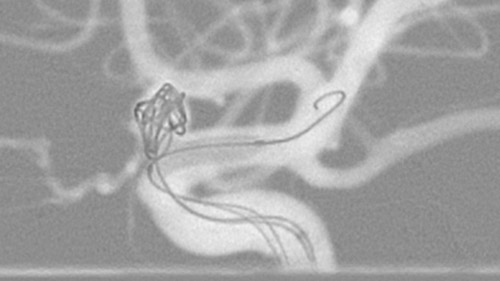

Dynamic 3D Roadmap provides a sustainable 3D roadmap to support interventional procedures. Dynamic 3D Roadmap matches the real-time 2D fluoroscopy images with the 3D-RA reconstruction of the vessel tree. It provides a 3D real-time insight of the advancement of the guide wire, catheter and coils through complex vessel structures. The Unsubtracted 3D Roadmap option reduces subtraction artifacts caused by patient breathing and movements, providing a clear roadmap during abdominal and thoracic interventions.

Live 3D Roadmap allows you to follow the advancement of guidewires, catheters and coils in real-time. It automatically adapts in real-time to changes in C-arm angulation and rotation, table movement, field of view and source-image distance.